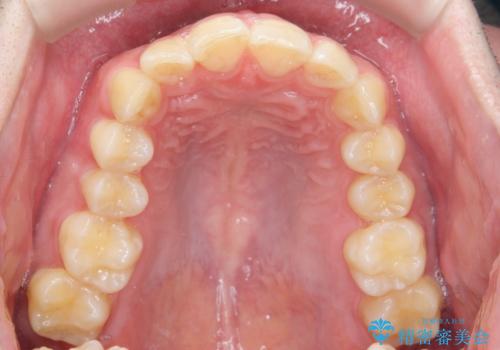

前歯のがたつきをなおしたい マウスピース矯正

- 気になる前歯のがたつきをきれいにしたい。と矯正治療を希望され来院されました。

大きな歯列の乱れはないため、倒れ込んでいる奥歯の傾きの改善、前歯のがたつきを改善する治療を計画します。

見た目が良くなっただけではなく、歯ブラシがしやすくなった!と治療後の歯並びに喜んでいただくことができました。